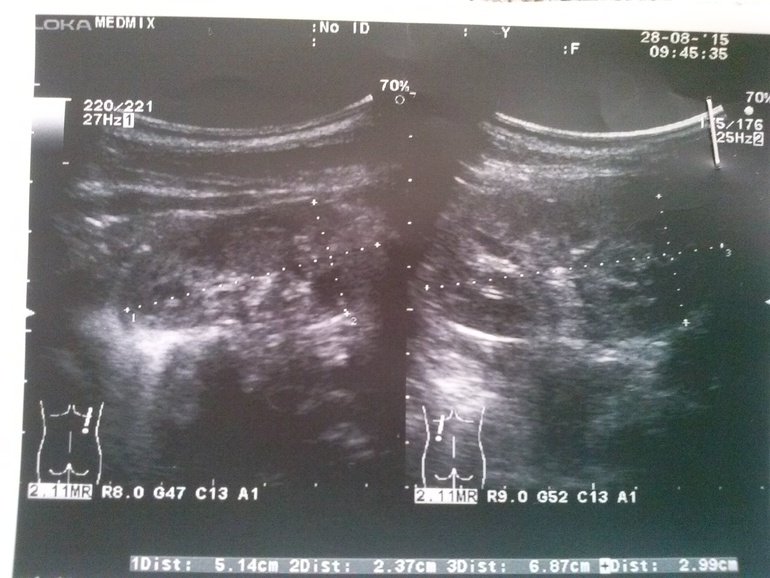

Добрый день. У меня сыночку в месяц по УЗИ поставили мегауретер, в 3 месяца гипоплазия правой почки. Сейчас нам 8 месяцев, все это время сдавали анализ мочи, все было в норме, пили канефрон. В 8 месяцев прошли обследование, цистографию и урографию. Выявили рефлюкс 3-4 степени правой почки. Через месяц назначено введение коллагена. А еще врач говорит что скорее всего придется удалить почку правую, но почему не понятно. Не уже ли обследование показало что то страшное? посмотрите пожалуйста.

Здравствуйте Валентина. Для решения вопроса об объеме операции вам будут проводить другие исследования (в частности нефросцинтиграфию), которые будут оценивать именно секреторную функцию почки. Пока, видимо, идет речь о ликвидации ПМР